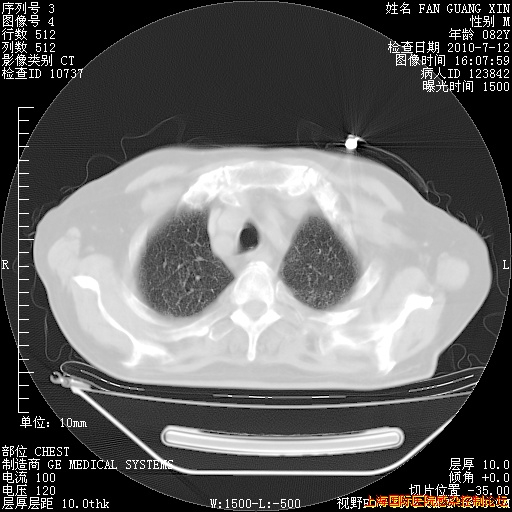

6月12日纵膈窗

今天复查CT

今天CT

整整相隔30天的肺部CT好像有所好转啊。甲强龙减量第3天,需要观察体温。